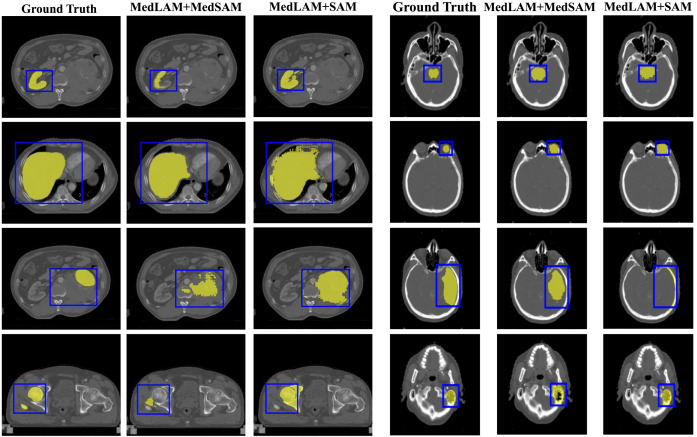

图6. 使用预训练的MedSAM和SAM,在经过MedLAM地标定位后,在WORD和StructSeg头颈部数据集上进行分割结果的可视化示例。